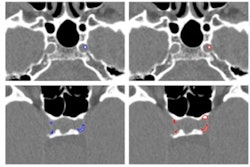

A recent analysis of the CT data published in RöFo disclosed calcifications in the chest, carotid artery, and various arteries of the skull base. The presence of arteriosclerotic plaques confirms ötzi's case as one of the oldest known incidents of vascular calcifications and also suggests the importance of genetic disposition as a trigger for coronary atherosclerosis, lead author Dr. Patrizia Pertner of Bolzano Hospital told Nachrichten.